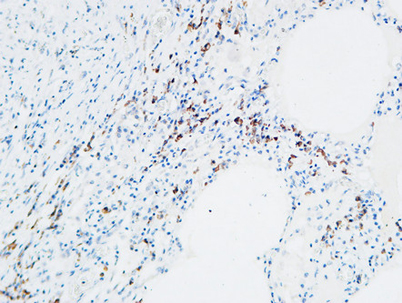

MPO rabbit pAb

Product name: MPO rabbit pAb

Reactivity: Human;Mouse;Rat

Alternative Names: MPO; Myeloperoxidase; MPO

Dilutions: IHC-p: 100-300.Western Blot: 1/500 - 1/2000. ELISA: 1/20000. Not yet tested in other applications.

Immunogen: The antiserum was produced against synthesized peptide derived from the N-terminal region of human MPO. AA range:41-90

Cellular localization: Lysosome.

Background: Myeloperoxidase (MPO) is a heme protein synthesized during myeloid differentiation that constitutes the major component of neutrophil azurophilic granules. Produced as a single chain precursor, myeloperoxidase is subsequently cleaved into a light and heavy chain. The mature myeloperoxidase is a tetramer composed of 2 light chains and 2 heavy chains. This enzyme produces hypohalous acids central to the microbicidal activity of neutrophils. [provided by RefSeq, Nov 2014],